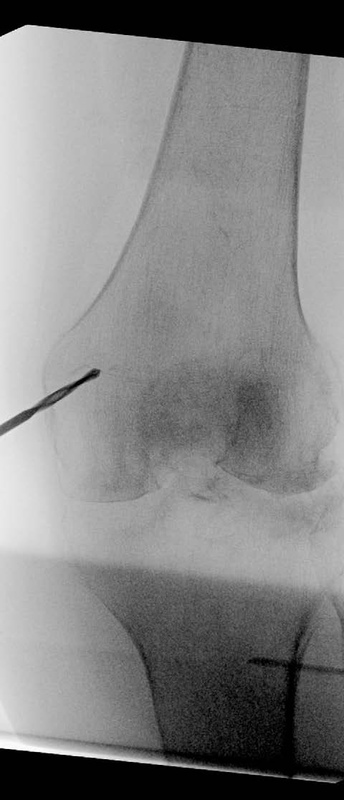

A 90-year-old patient presented with a periprosthetic femur fracture after a fall from a standing height fall. Patient is a community ambulator with no assistive walking device. X-rays revealed a long stem hip implant from a previous hemiarthroplasty. The fracture necessitated fixation and was treated operatively through a small incision in the medial distal femur. The guide wire was inserted to the tip of the stem before the implant was inserted. The IlluminOss implant was inserted, filled with liquid monomer, and cured with visible light. A plate and screw construct was placed laterally with screws extending into the hardened IlluminOss implant for support. Patient was allowed to weight bear as tolerated and reported no issues at follow up visit.